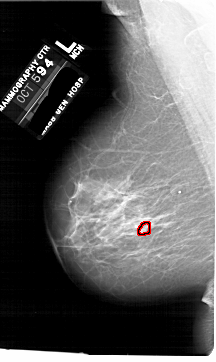

A_1760_1.LEFT_MLO

LEFT_MLO LINES 6871 PIXELS_PER_LINE 4096 BITS_PER_PIXEL 12 RESOLUTION 43.5 OVERLAY

FILE: A_1760_1.LEFT_MLO.OVERLAY

TOTAL_ABNORMALITIES 1

ABNORMALITY 1

LESION_TYPE CALCIFICATION TYPE PLEOMORPHIC DISTRIBUTION CLUSTERED

ASSESSMENT 4

SUBTLETY 2

PATHOLOGY BENIGN

TOTAL_OUTLINES 1

BOUNDARY